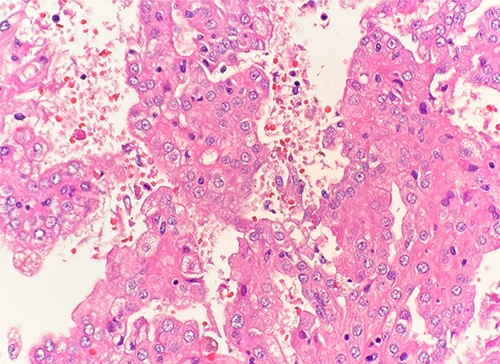

Microscopic examination revealed that clear cell RCC (Fig. 1), papillary RCC type 1 (Fig. 2), and papillary RCC type 2 (Fig. 3) were present in the right kidney, and papillary RCC type 2 was present in both kidneys. Immunostaining showed that tumor cells were positive for alpha-methyacyl-CoA racemase (Fig. 4), CD10, CK7, and vimentin, and negative for CD117.

Immunohistochemical stain reveals that tumor cells are positive for alpha-methyacyl-CoA racemase. IHC stain 40x.